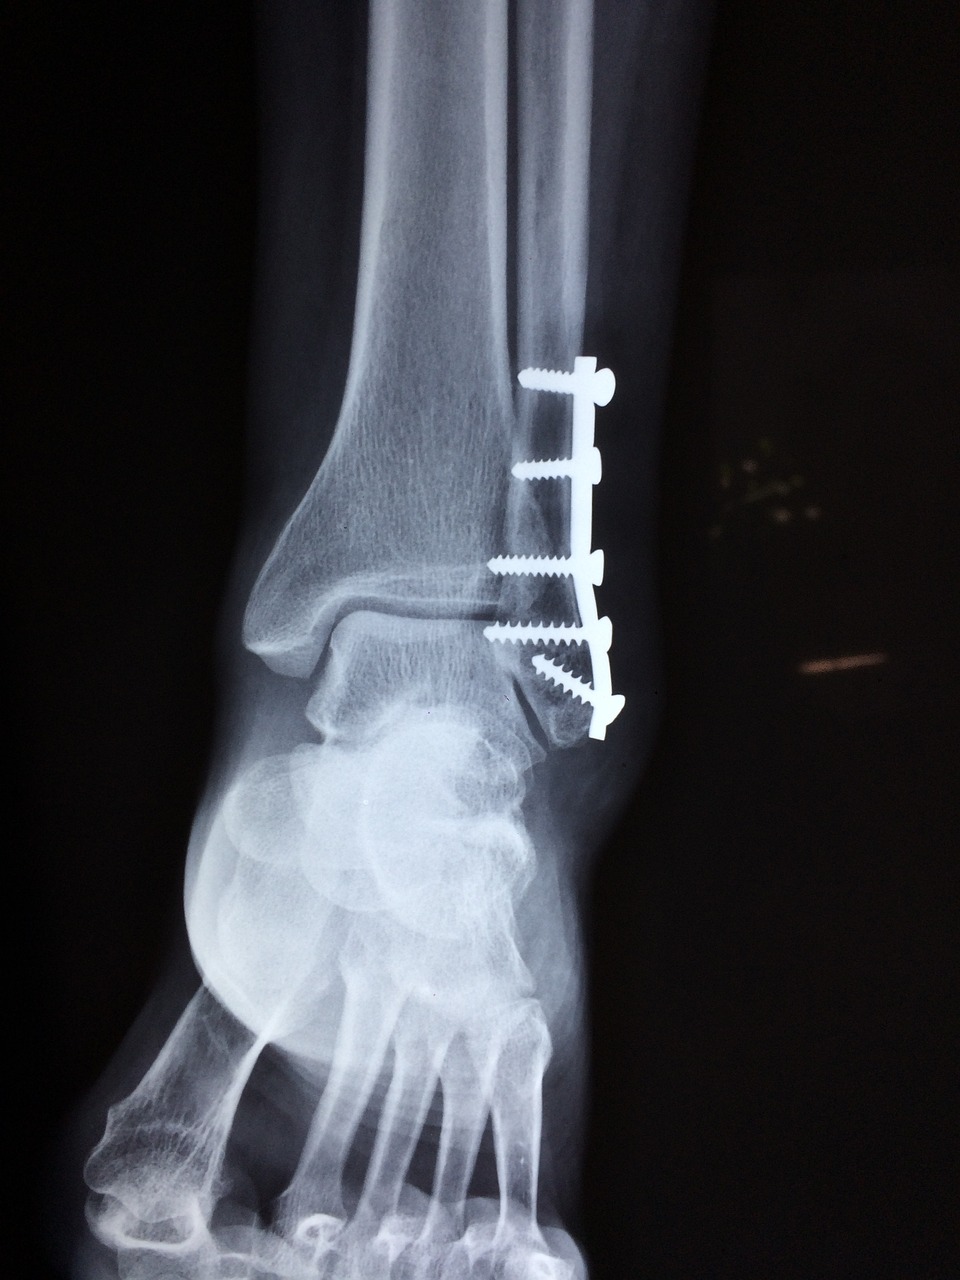

골절 간호기술이란 건 환자가 얼른 나을 수 있게 해주는 필수템이에요. 제대로 된 간호 기술로 골절 부위를 계속 체크하고 잘 돌봐줘야 해요. 간호사님이 붓기나 색깔 변화, 이상한 느낌, 혈액 순환이 잘 안 되는 문제 같은 걸 꼼꼼히 보셔야 하잖아요.

환자 한 명, 한 명마다 다 다르니까 개인별 맞춤 간호가 필요해요. 당신들은 의학 지식으로 환자의 특별한 필요를 알아내고 딱 맞는 간호 계획을 세워야 합니다. 그래야 환자분들이 가장 좋은 결과를 받을 수 있거든요.

그리고 우리 간호사님들, 골절 후 나타날 수 있는 합병증도 찾아내고 막는 게 엄청 중요해요. 예를 들어서 욕창이나 혈전 같은 문제들 말이죠. 제대로 된 간호와 주의로 이런 걸 예방할 수 있다니까 신경 써주세요! 이런 합병증들 때문에 회복 시간만 길어지고, 심하면 생명 위협받을 수도 있으니까 말이에요.